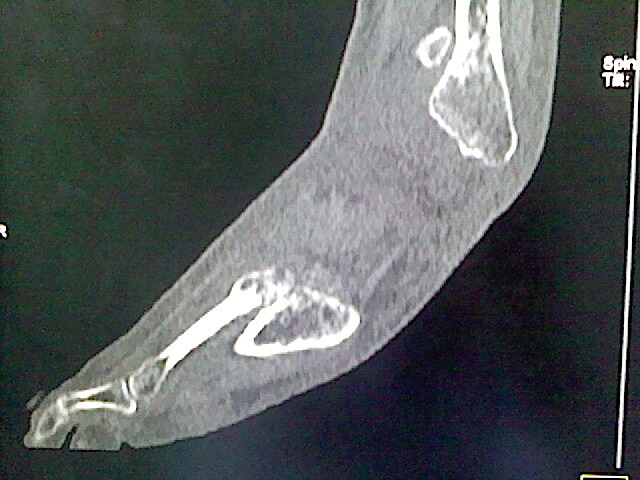

男,76岁,左小腿疼痛,不能站立

本例骨质改变主要表现为滑膜或韧带区的骨侵蚀融解(胫腓联合区骨质破坏无硬化边),距骨后部骨质破坏区有硬化边及死骨样改变.所以,本例考虑关节结核可能性大,绒毛膜结节性滑膜炎多发于中年,且极少见于膝髋以外的关节,骨质硬坏也以压陷吸收为主,有明显的硬化边,骨膜增生呈结节状(可以mr鉴别),所以本例暂除外.

另不除外可引起相似表现的其他炎症如布氏杆菌性关节炎等